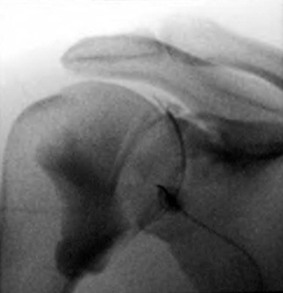

CT of the shoulder is performed primarily as a means of evaluating the osseous structures after trauma.12,13 Multidetector CT examinations with oblique sagittal and oblique coronal reconstructions can accurately detect the extent of humeral head and neck fractures. The precise number of fracture fragments, as well as the extent of displacement and angulation of fracture fragments, is accurately depicted. The scapula is a complex anatomic structure composed of the body, coracoid and acromion processes, and the glenohumeral articular surface. As a result, the full extent of scapular fractures is difficult to describe fully using conventional radiography, whereas the multiplanar capabilities of CT make it ideal for evaluation of complex scapular fractures. After glenohumeral dislocation, CT examination is the best modality to depict the size and position of a glenoid rim fracture fragment, which can be an important part of presurgical planning (Fig. 44-4). CT with three-dimensional reformations and subtraction of the humeral head is also the modality of choice for preoperative assessment of glenoid bone loss after anterior dislocations.14-16